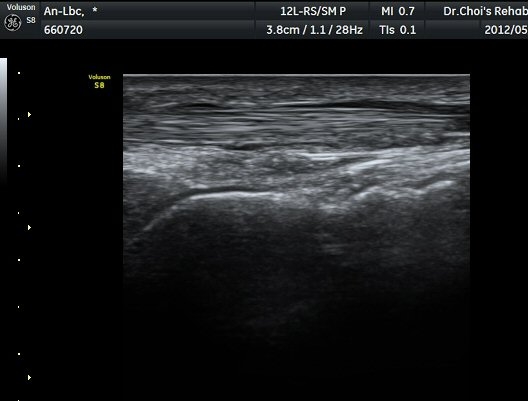

¹ß¸ñ ¾Õ Ⱦ´Ü¸é°Ë»ç¿¡¼­ Àü°æ°Ç(TA), ¾öÁö½ÅÀü°Ç(EPL), ¹ß°¡¶ô½ÅÀü°Ç(EDL)ÀÇ ºÎÁ¾ ¹×

°Ç ÁÖÀ§ ¼ö¾× Àú·ù°¡ °üÂûµÈ´Ù(»çÁø 1, 2). °ÇÀÇ ºñÈÄ¿Í ¼ö¾×Àú·ù´Â °ÇÃø(»çÁø 4)°ú ºñ±³Çϸé

¶Ñ·ÈÇÏ´Ù. Àü°æ°Ç Á¾´Ü¸é°Ë»ç¿¡¼­ °ÇÀÇ ºÎÁ¾°ú °Ç ÁÖÀ§ ¼ö¾× Àú·ù°¡ °üÂûµÈ´Ù(»çÁø 3). °ÇÀÇ